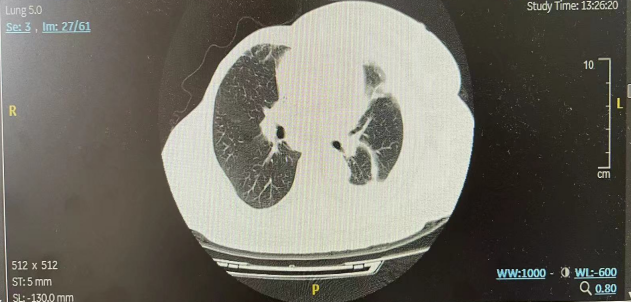

二线治疗前(2022年7月)患者再次出现高热,于外院诊断肺炎(图2)。抗炎治疗3周后,肺炎有所好转(图3),体温恢复。

图2.二线治疗前胸部CT示左肺炎

图3.抗炎治疗3周后胸部CT示左肺炎好转